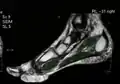

Large mediastinal angiolipoma

Large mediastinal angiolipoma